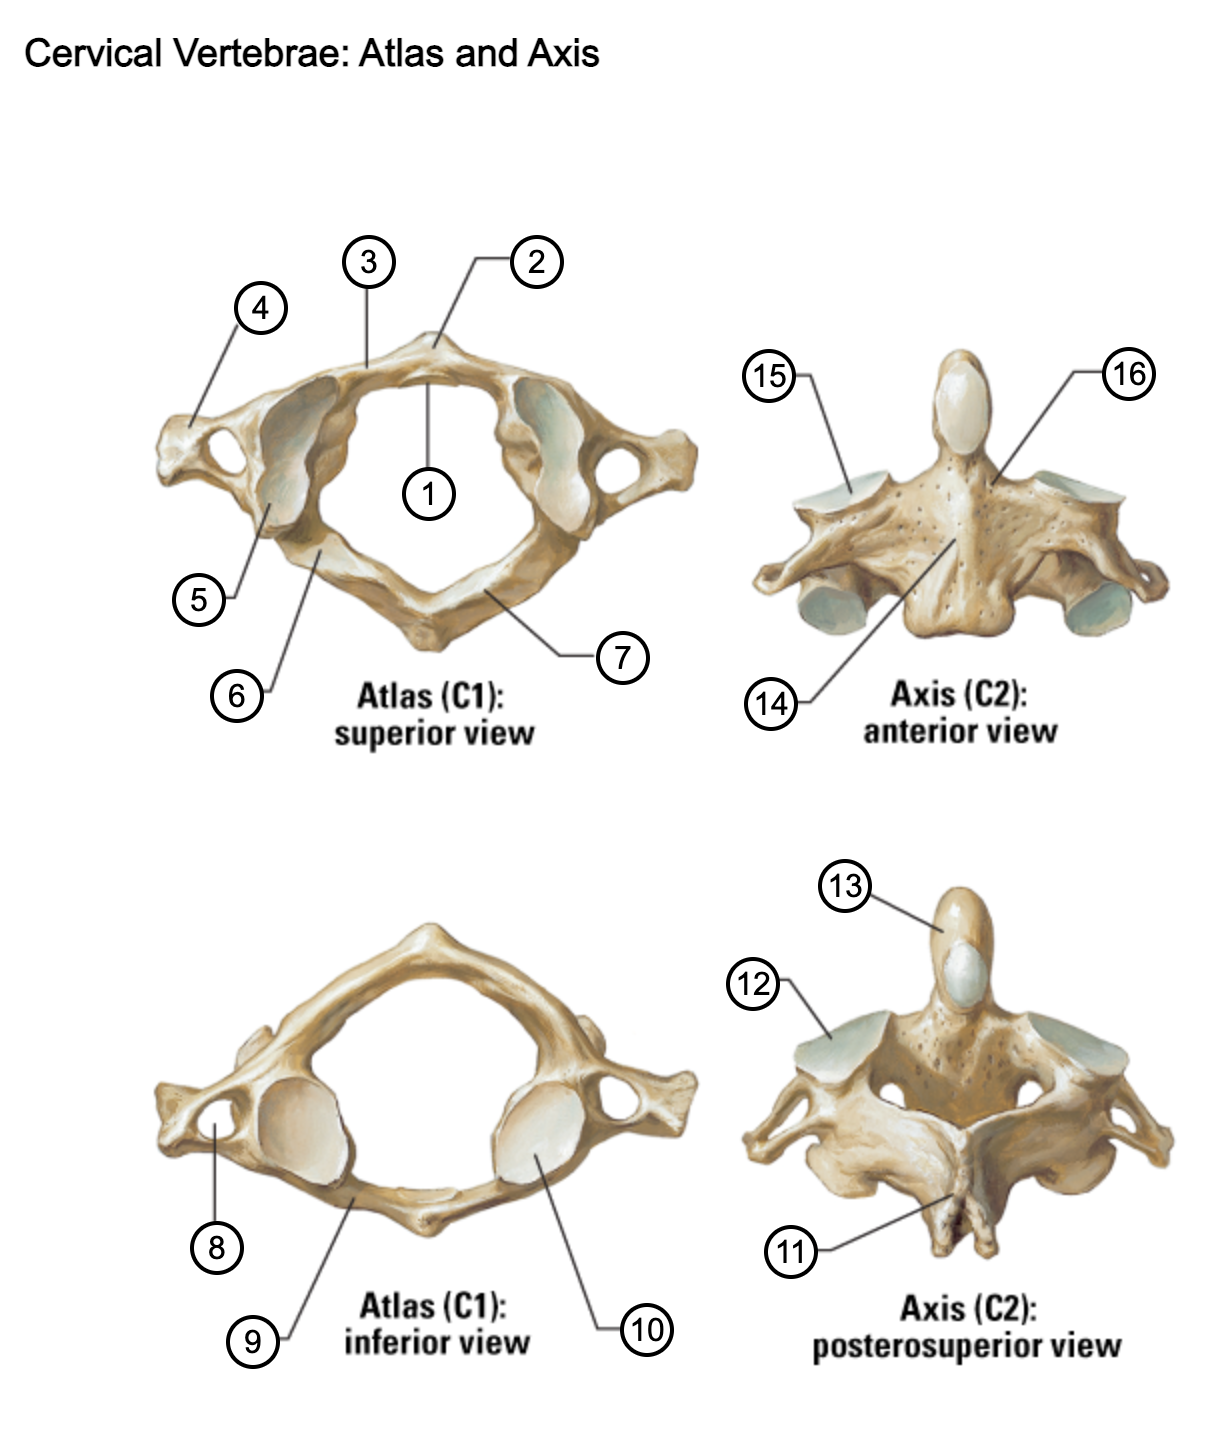

1

facet for dens

2

anterior tubercle

3

anterior arch

4

transverse process

5

superior articular surface of atlas

6

groove for vertebral artery

7

posterior arch

8

transverse foramen

9

anterior arch

10

inferior articular surface of atlas

11

spinous process

12

superior articular facet

13

dens of axis

14

body of axis

15

superior articular facet for atlas

16

pedicle of vertebral arch